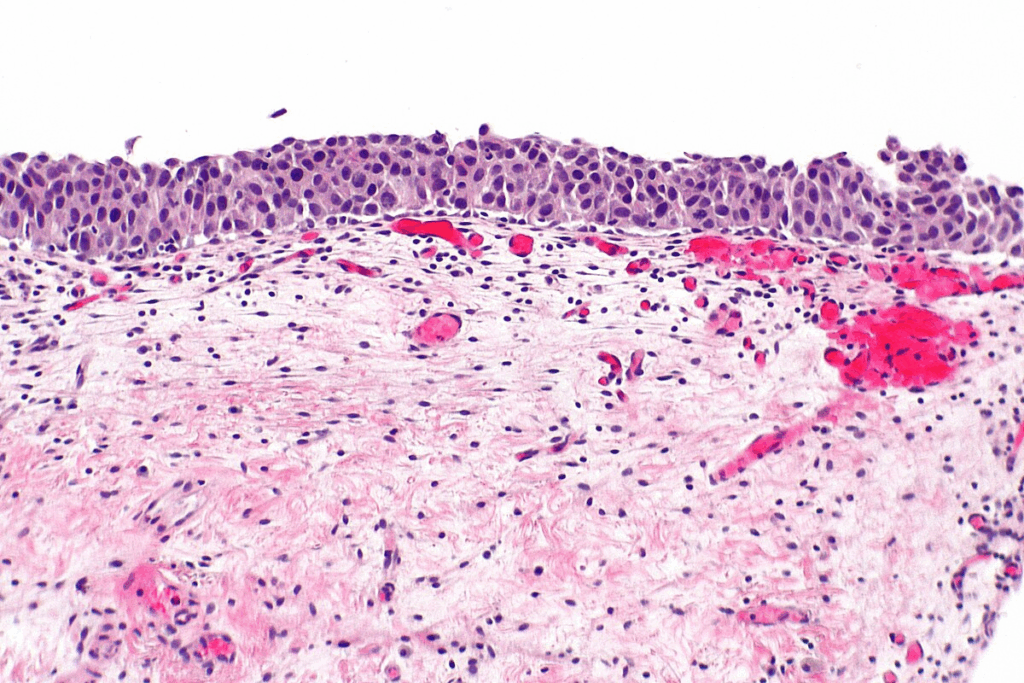

When we look at carcinoma in situ cells under a microscope, they show signs of being cancerous. They have irregular shapes and abnormal nuclei. These signs show they could become cancer, but they’re stuck in their original tissue.

A key trait of carcinoma in situ is that it stays in the tissue where it started. The cancer cells haven’t crossed the basement membrane. This thin layer of tissue keeps them from spreading.